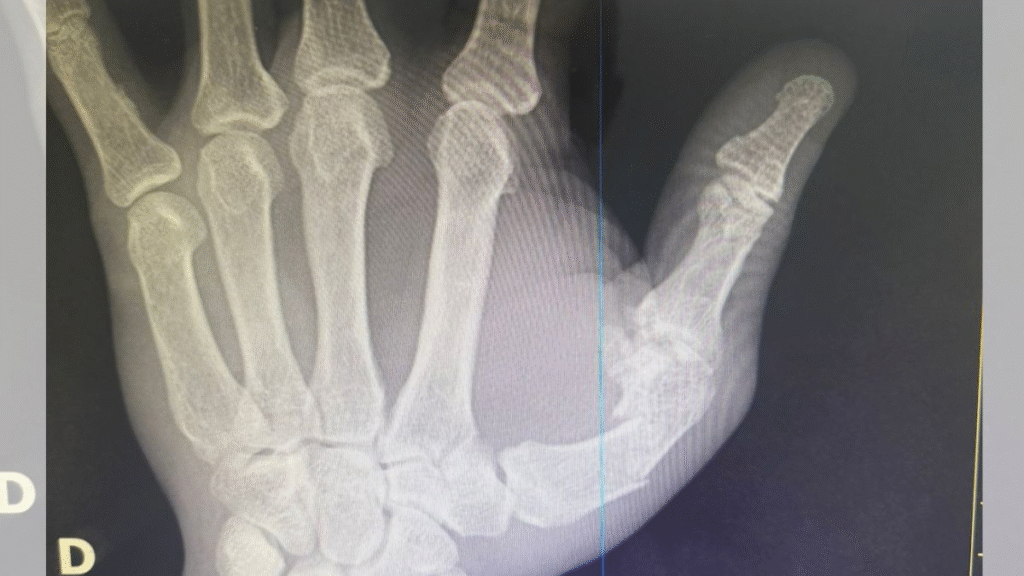

Acelino Popó Freitas passa por cirurgia na mão esquerda na tarde desta segunda-feira (29), em Salvador. O ex-campeão mundial de boxe sofreu a lesão na confusão generalizada entre as equipes após a luta com Wanderlei Silva, no último sábado (27). Além da fratura na mão, a assessoria do lutador informou que exames de imagem revelaram um sangramento interno na cabeça, apesar de não apontar nenhum outro dano.

“Está tudo bem com os exames de cabeça, não quebrou nada, teve sangramento interno. Porém, quebrou a mão na confusão, algo que nunca aconteceu em 35 anos de profissão. Ele acabou de entrar na sala de cirurgia, que deve durar em torno de 2h30. Estamos todos em orações para que dê tudo certo”, informou a assessoria de imprensa de Popó.